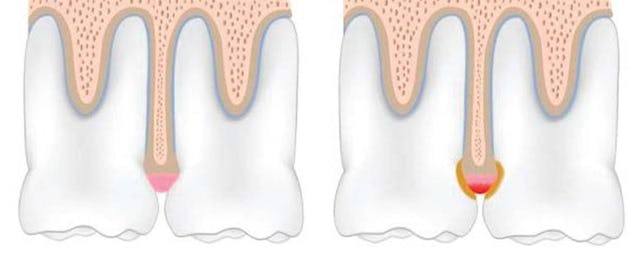

Entzündung-Knochenverlust

Im Bild links eine schematische Darstellung einer gesunden Zahnfleischsituation ohne Entzündung

Auf dem Bild rechts sehen wir eine Kariesbildung im Anfangsstadium und bakterieller Kontamination. Aus der Zahnfleischentzündung resultiert auch eine Entzündung des so genannten Alveolarknochen über und führt zu dessen Abbau. Sobald dieser Abbau (Knochenverlust) ein gewisses Ausmass erreicht hat, fängt der Zahn an zu wackeln und ist damit schwer kompromittiert. Es ist eine Frage der Zeit bis er nicht mehr erhaltungswürdig ist und gezogen werden muss.